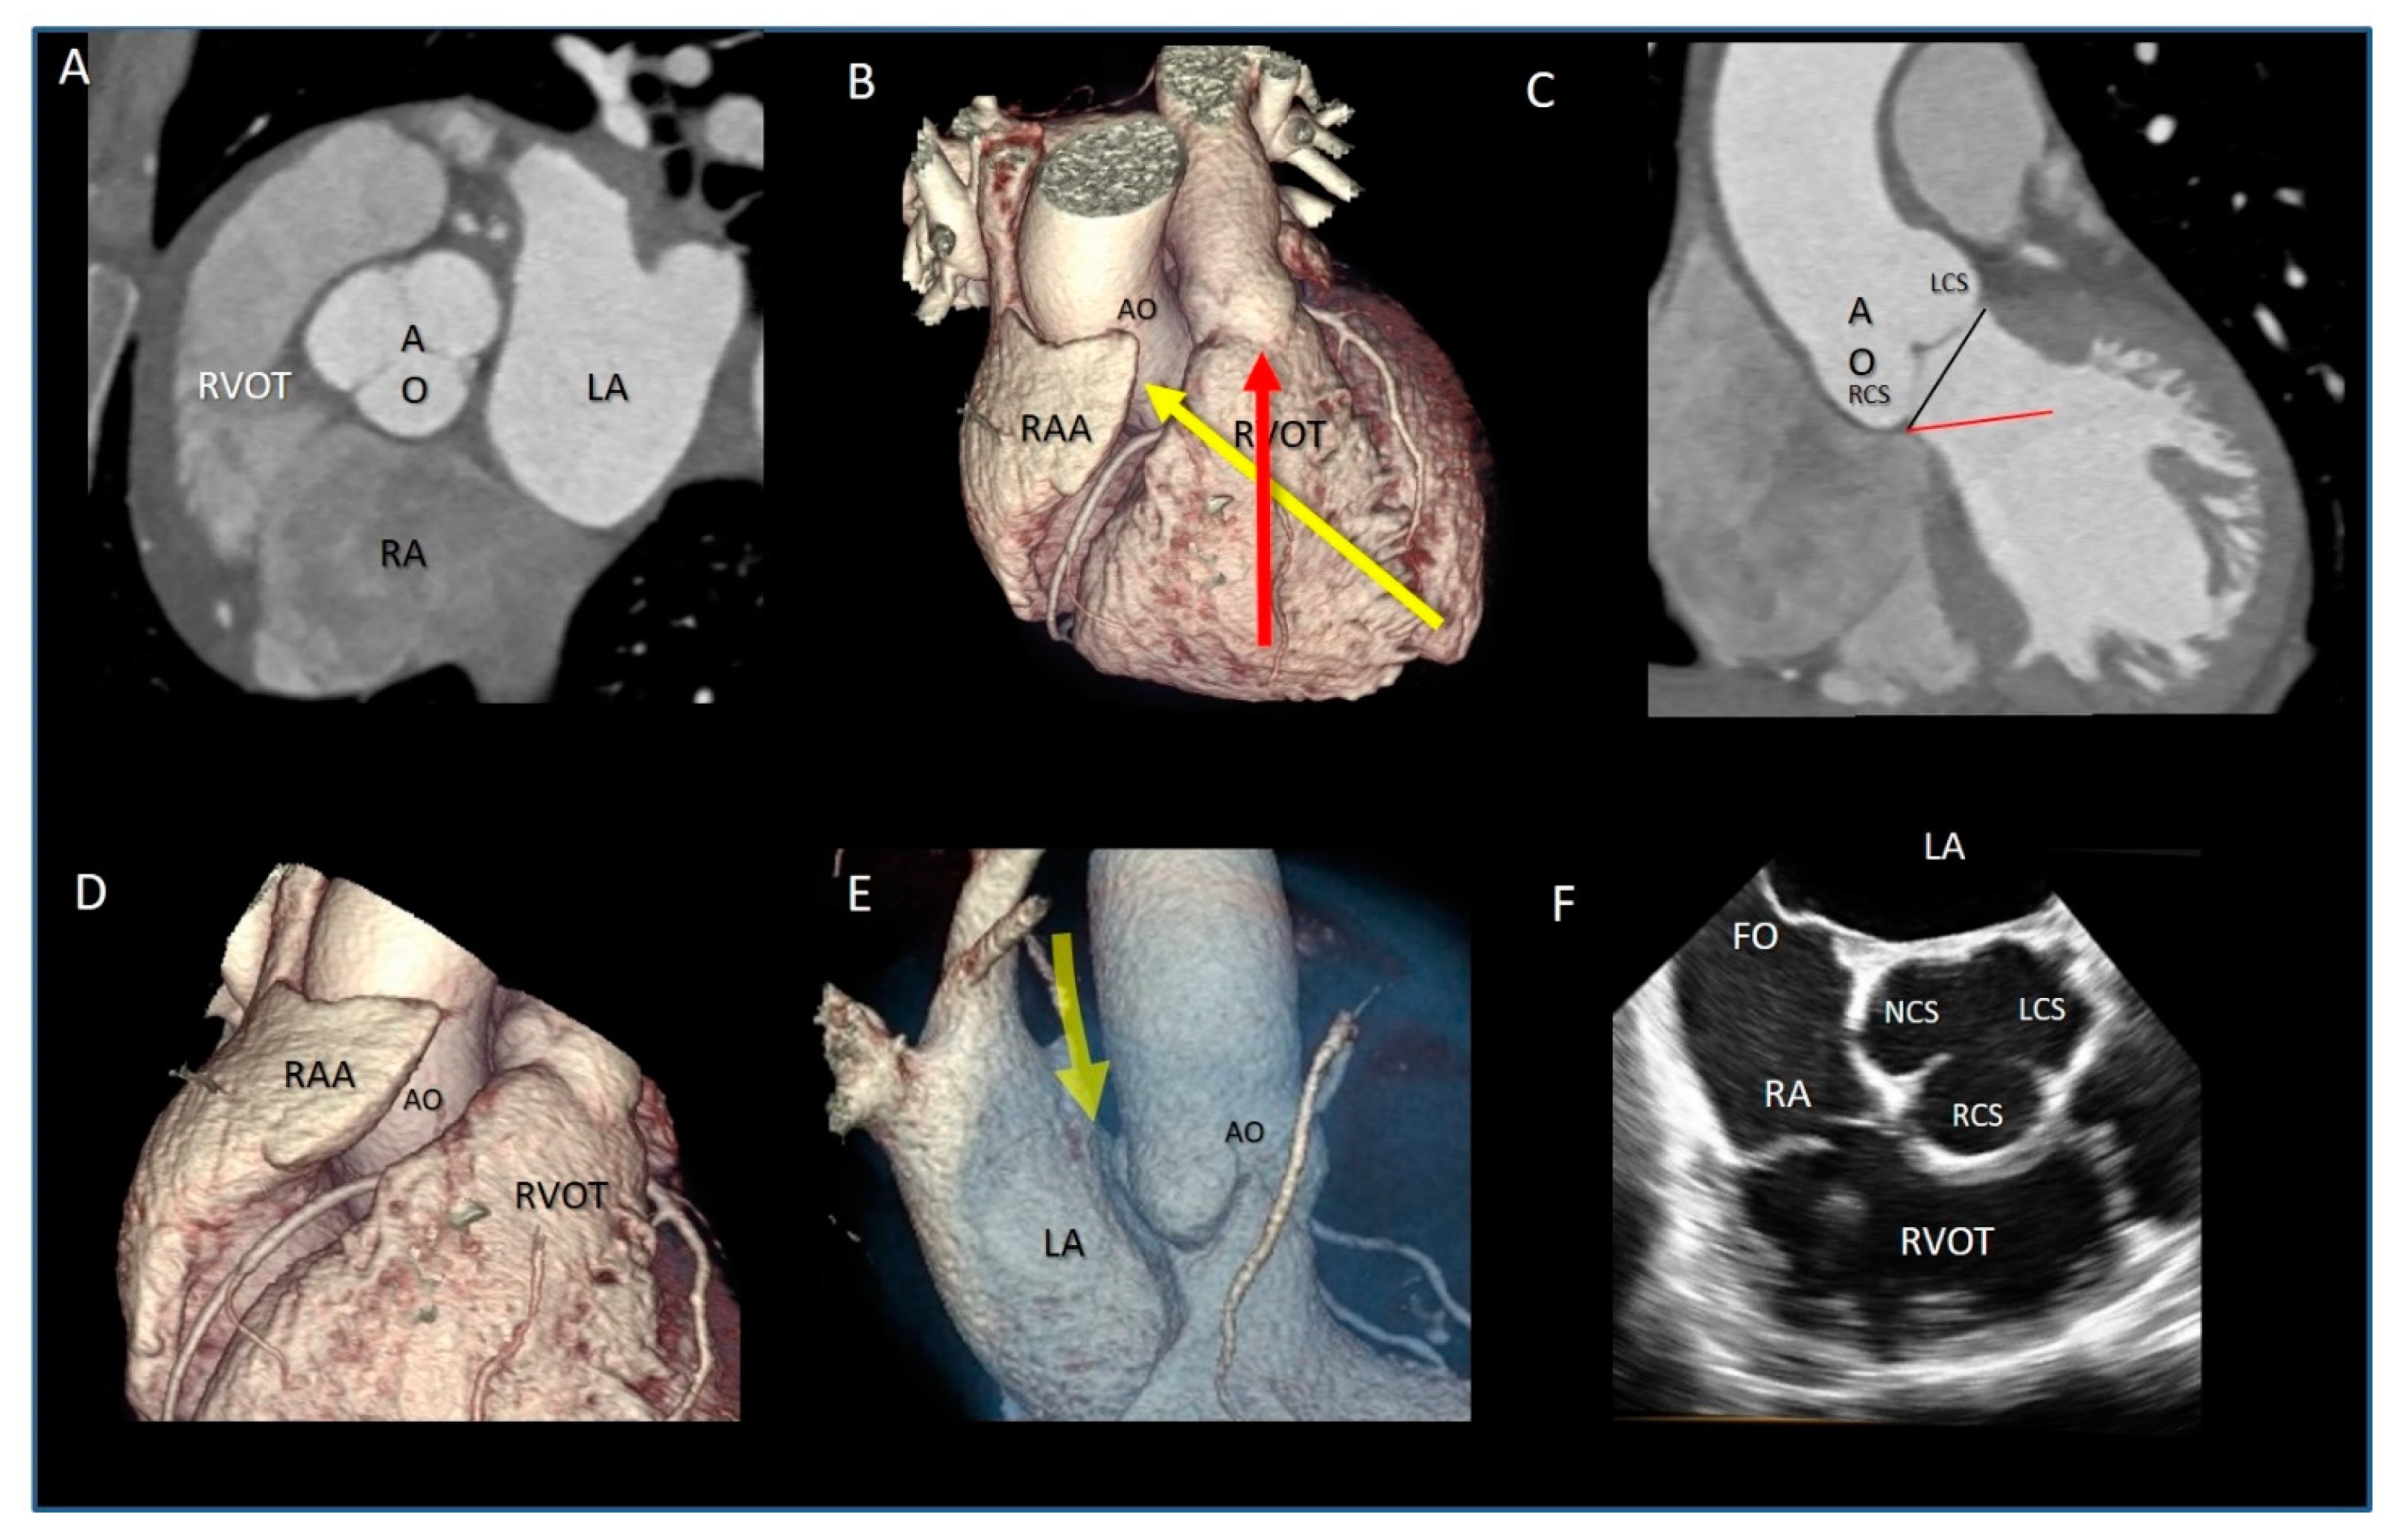

| Ventricular–arterial junction | The term ventricular–arterial junction describes the border between the ventricular myocardium and the fibroelastic structure of the aortic root. Contrary to the right AV junction, where the pulmonary root is entirely supported by the muscular infundibulum, only the left and the right coronary sinuses are partially supported by the myocardium (see text), being the remaining extent of the aortic root supported by fibrous tissue (MS = membranous septum; see text and references [12,13]). | ![]() |